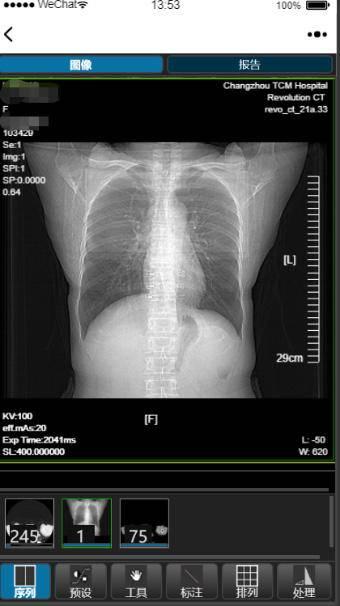

扬子晚报网4月9日讯(通讯员 王唯 采访人员 张斌)“云影像”通俗地说就是没有胶片 , 能够通过手机 , ipad等智能终端查看、诊断和分享病人的影像资料 。 今天上午 , 采访人员从常州市中医医院获悉 , 该院正式上线了“互联网+云影像”服务 , 通过云平台及互联网医院平台 , 遵从“共建、共生、共享”互联网思维 , 实现了医学影像与互联网技术的无缝对接 , 标志着常州中医院“互联网+”医疗服务步入了“高、新、尖”阶段 。

目前“云影像”服务涵盖了CT、MRI、DR等方面检查影像及报告 , 患者只需关注“常州市中医医院”公众号 , 点击医疗服务进入互联网医院 , 就能在手机端随时随地轻松查看检查报告和云影像 , 快捷又方便 。

“云影像”服务的上线是常州中医院深化医改 , 探索互联网医疗服务新模式 , 提高医疗保障水平和服务满意度的新举措 。 对病人来说 , 只要在放射科完成拍片检查 , 患者就可以直接在手机上查看影像图像及检查报告 , 若更换医院看病 , 也避免了重复检查 , 降低了患者的就医成本;对医生来说 , 减少了等待影像胶片及检查报告的时间 , 可以在电脑端随时随地的查看相应患者的影像及检查报告 , 很好地解决了接诊过程中长时间等待的麻烦 。 对医院来说 , 大大节省了检查报告和胶片的耗材成本、胶片报告自助打印机的维护成本 , 大大提高了医疗效率 , 缩短了服务流程 。